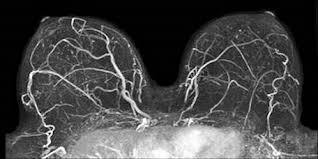

Yesterday was the Breast MRI. You lay on this weird little table, face down with your chest in holes facing down. Its REALLY uncomfortable. Then you face is in a pillow thing like on a masseuse table but without essential oils. Then you put in ear plugs and they shove you in the machine.